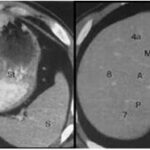

Los VIII segmentos anatómicos hepáticos están definidos por la organización de los sistemas venosos hepático y portal (ver Anexos 2 y 3). Asimismo, cada segmento tiene un flujo circulatorio y drenaje biliar independiente. Por tal motivo es posible eliminar uno o más segmentos y aun así no interrumpir el flujo sanguíneo ni biliar de los demás segmentos.(1)

El hígado se puede dividir en cuatro secciones: la sección anterior derecha (segmentos V y VIII), sección posterior derecha (segmentos VI y VII), sección medial izquierda (segmento IV) y sección lateral izquierda (segmentos II y III) (ver Anexo 4).

La hiperplasia nodular focal es el segundo tumor benigno más frecuente después del hemangioma. Tiene mayor incidencia en mujeres jóvenes. Histológicamente es un tumor hiperplásico que conserva los mismos componentes del tejido hepático normal, pero con una arquitectura alterada (hepatocitos normales + células de Kupffer + conductos biliares primitivos no conectados con la vía biliar normal). Presentan una cicatriz central de tejido fibroso con estructuras vasculares dilatadas y ectásicas. En la tomografía multicorte sin contraste intravenoso se evidencia como una lesión homogénea bien definida, hipo o isodensa con respecto al parénquima hepático. En la tomografía multicorte multifásica, después de la administración del medio de contraste, tiene un comportamiento típico.

- Fase arterial: reforzamiento intenso.

- Fase portal: es isodenso o ligeramente hiperdenso con respecto al parénquima.

- Fase tardía: lesión totalmente isodensa, no se visualiza, excepto porque puede producir efecto de masa sobre el parénquima adyacente.

La cicatriz central (Anexos 21 y 22), al estar menos vascularizada, no refuerza en fase arterial. Sin embargo, en fase tardía muestra hiperdensidad cuando ya el resto de la lesión se ha hecho isodensa.(18)